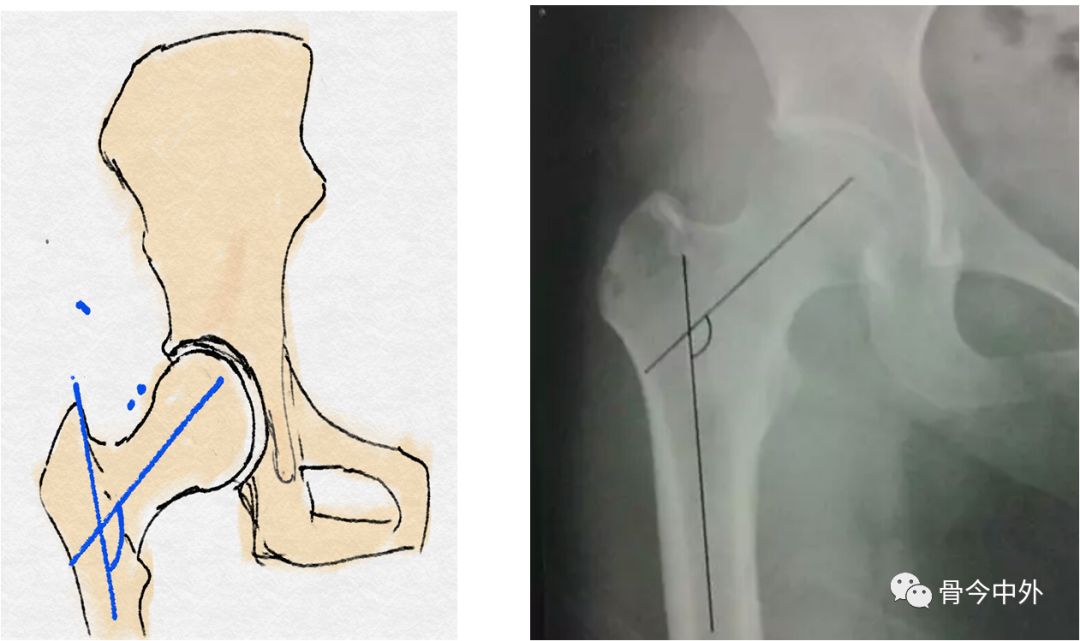

1、股骨的评估

股骨干轴线与股骨颈轴线的交角(正常:110°~140°)

股骨颈的长轴与股骨干纵轴之间形成的角度称为颈干角,又称内倾角。正常值在110~140°之间,男性平均为132°,女性平均为127°。颈干角随年龄的增大而减小,儿童的颈干角大于成年人,儿童平均为151°。颈干角大于正常值为髋外翻,小于正常值为髋内翻。